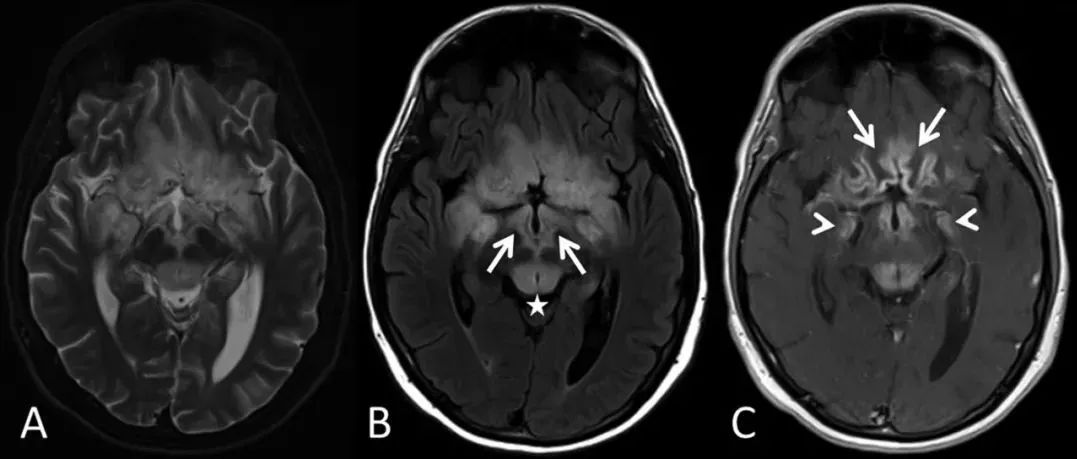

19岁男性,表现为逐渐加重的疲劳、白天过度嗜睡和头痛2月。患者被注意到有意识模糊、定向障碍和幻觉。查体时患者神志清,能够遵嘱完成简单的任务。但无法流利说话或回答问题,并表现出不受约束的行为(disinhibited behavior)。由于患者的脑病表现,行神经影像学检查,结果显示下丘脑、额叶下内侧、扣带回、颞叶内侧和中脑背侧对称性T2WI和液体衰减反转恢复序列(FLAIR)高信号(图1)。(图1:中脑喙侧水平的轴位MRI可见[A]额叶下内侧T2高信号;[B]下丘脑、乳头体[箭]、背侧中脑和导水管周围灰质[*]FLAIR高信号;[C]颞叶内侧[箭头]和额叶下内侧[箭]T1增强后强化;侧脑室水平的轴位MRI可见[D]扣带回T2高信号;[E]胼胝体膝部膝FLAIR高信号[箭];[F]扣带回T1增强后强化[箭])...